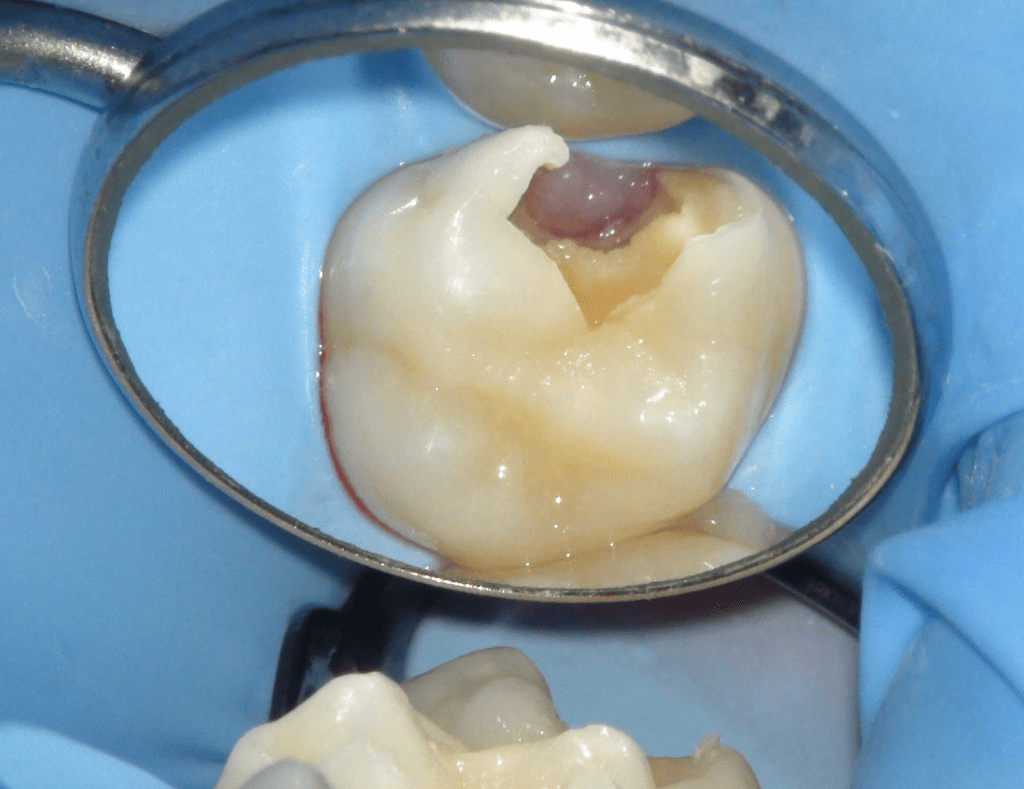

Pulpotomía biodentine + reco preendio